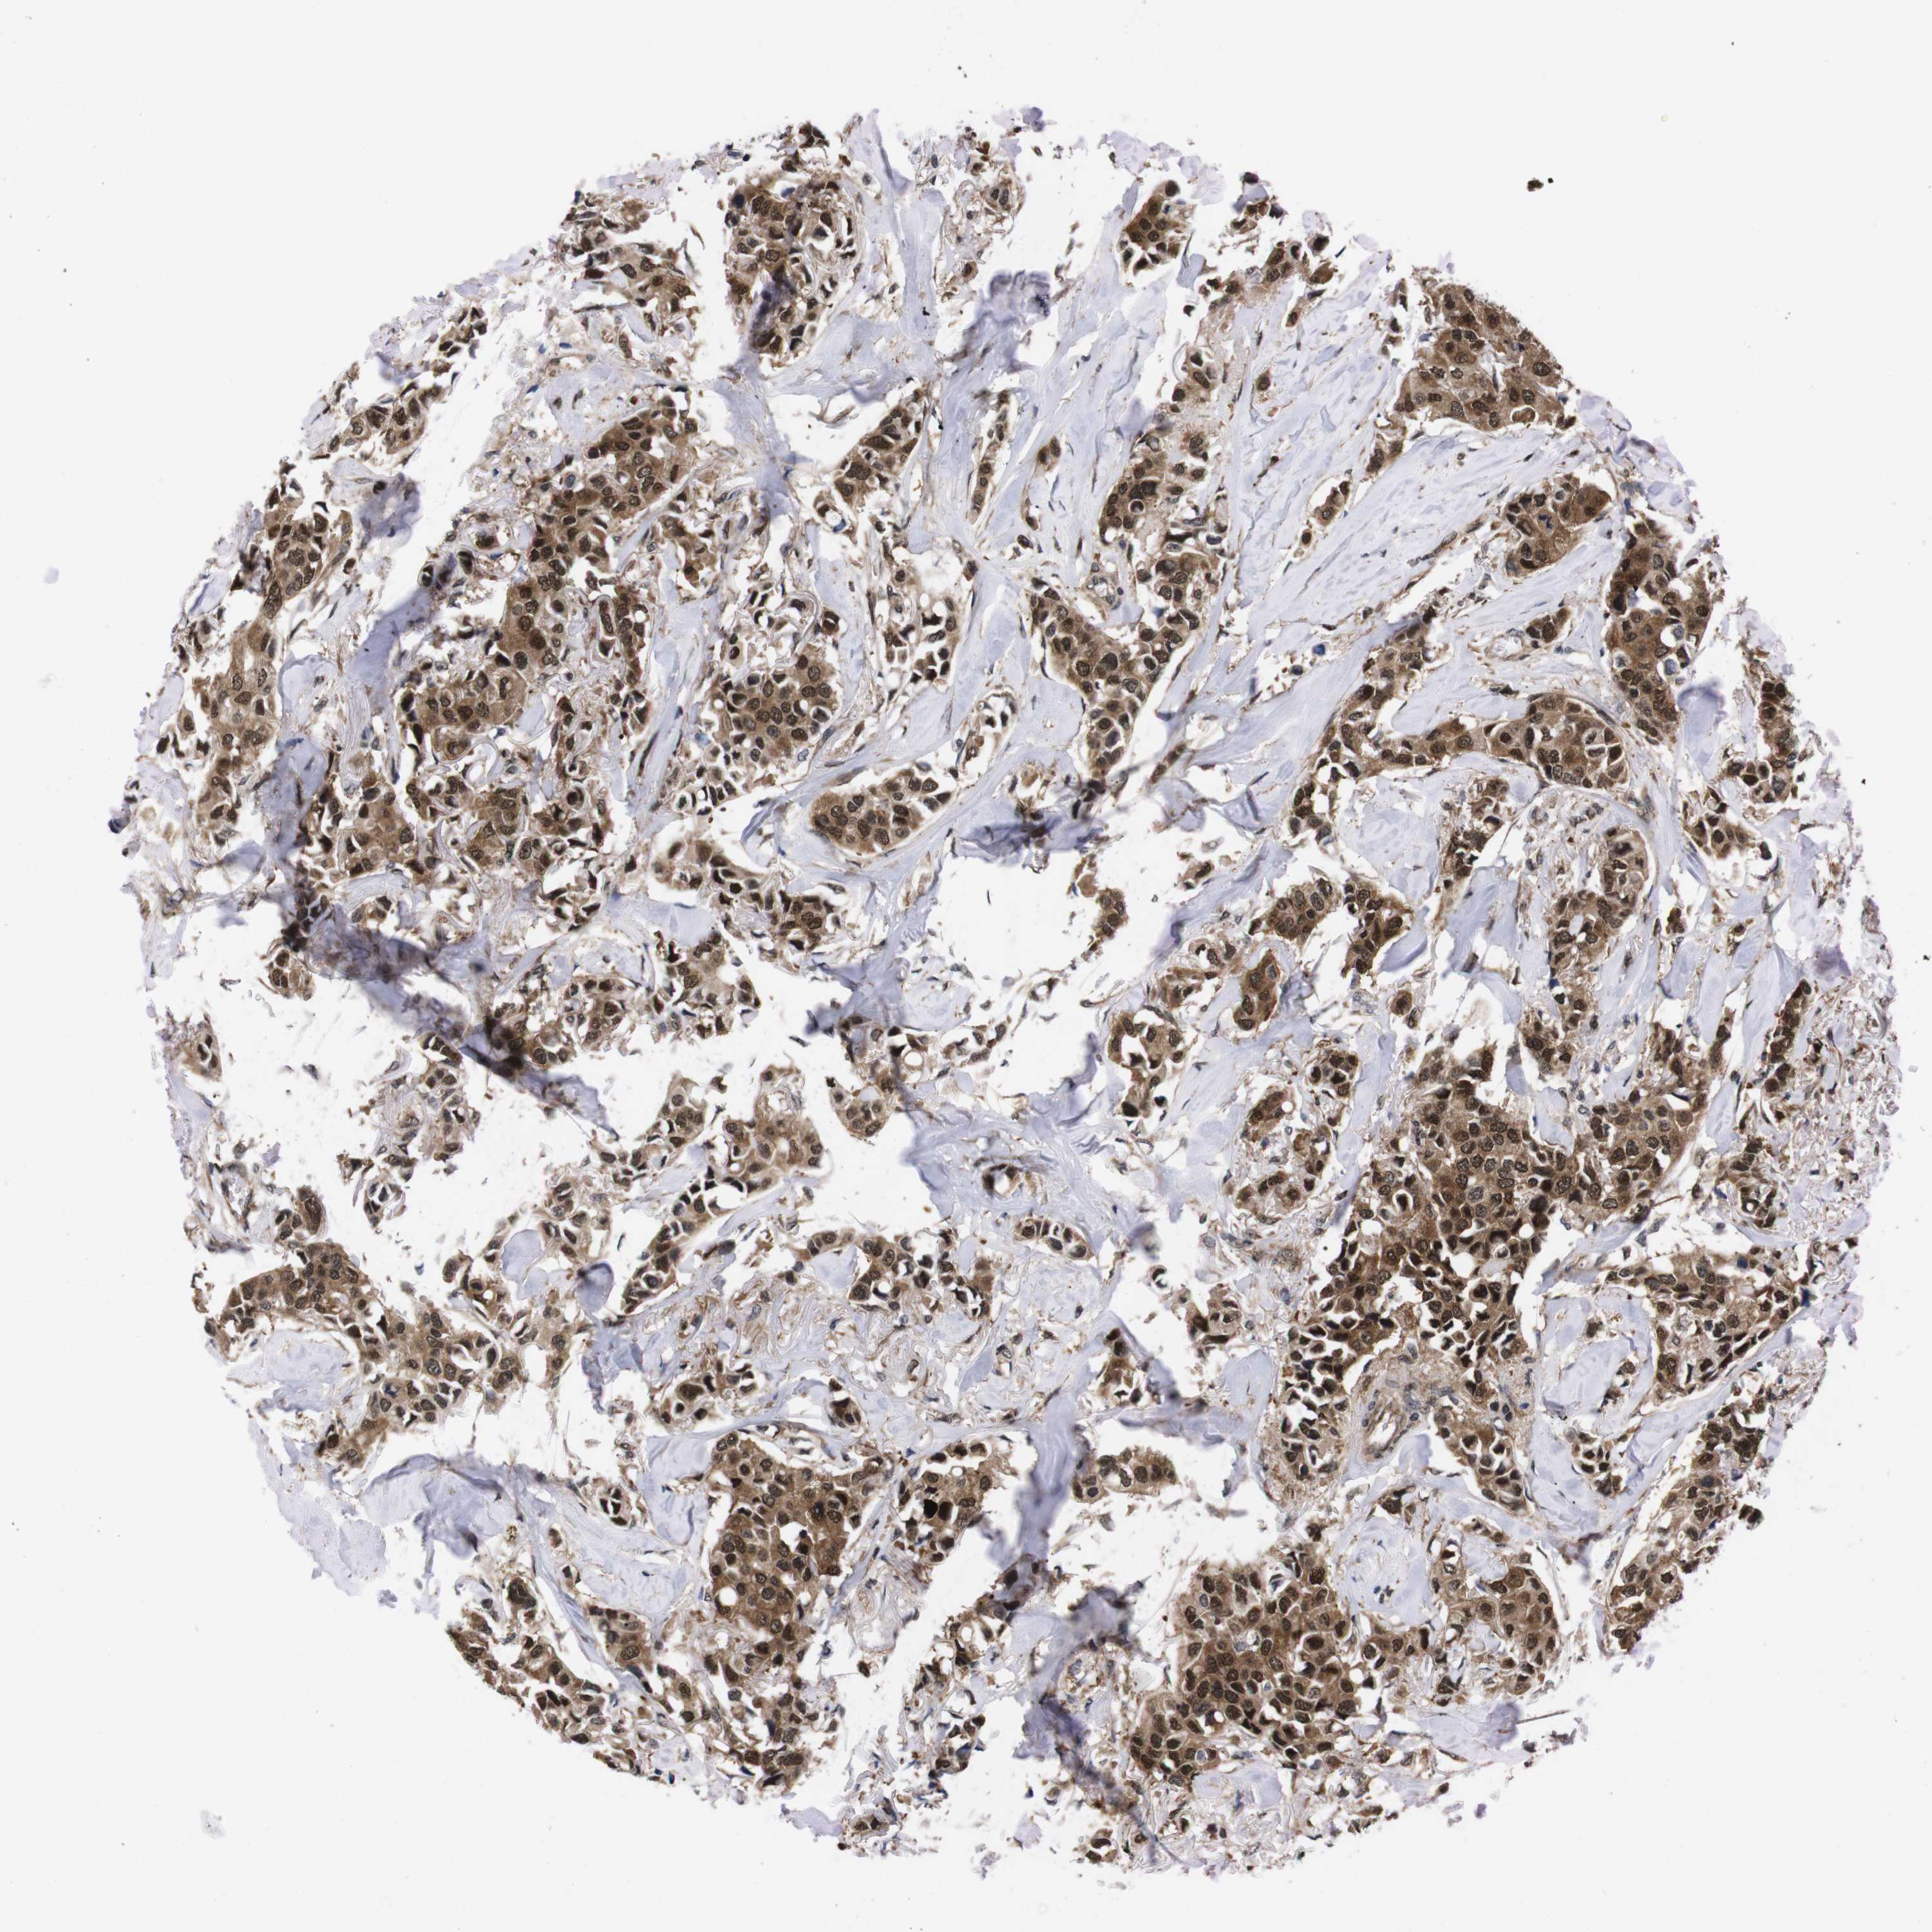

CANCER BREAST CANCER Show tissue menu

Breast cancer

Human cancer

UBQLN2 is potential prognostic, high expression is unfavorable in Breast Invasive Carcinoma (TCGA)